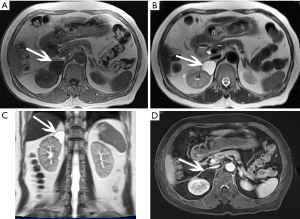

Αφού επιβεβαιωθεί η διάγνωση, η CT, η μαγνητική τομογραφία (MRI) ή ο συνδυασμός των δύο χρησιμοποιούνται για τον εντοπισμό του όγκου και τον καθορισμό της ενδεδειγμένης θεραπείας.

Η αξονική και η μαγνητική τομογραφία των επινεφριδίων μπορεί να αναδείξουν το αδένωμα που είναι υπεύθυνο για το σ. Cushing. Αντιθέτως, η ευαισθησία τους σε περιπτώσεις αμφοτερόπλευρης οζώδους υπερπλασίας του φλοιού είναι περιορισμένη. Η MRI με χρήση γαδολινίου ως σκιαγραφικού μέσου και με λεπτές τομές στην περιοχή του εφιππίου μπορεί να επιβεβαιώσει την παρουσία ενός αδενώματος υπόφυσης ή υπερπλασίας σε ασθενείς με υποψία συνδρόμου Cushing.

Η αξονική τομογραφία θώρακα-κοιλιάς είναι χρήσιμη για την ανάδειξη όγκων (π.χ. πνεύμονα) που προκαλούν έκτοπη παραγωγή ACTH. Αν η πηγή της έκτοπης ACTH είναι νευροενδοκρινής όγκος, το σπινθηρογράφημα υποδοχέων σωματοστατίνης (OCTREOSCAN) μπορεί να βοηθήσει στην εντόπισή του.